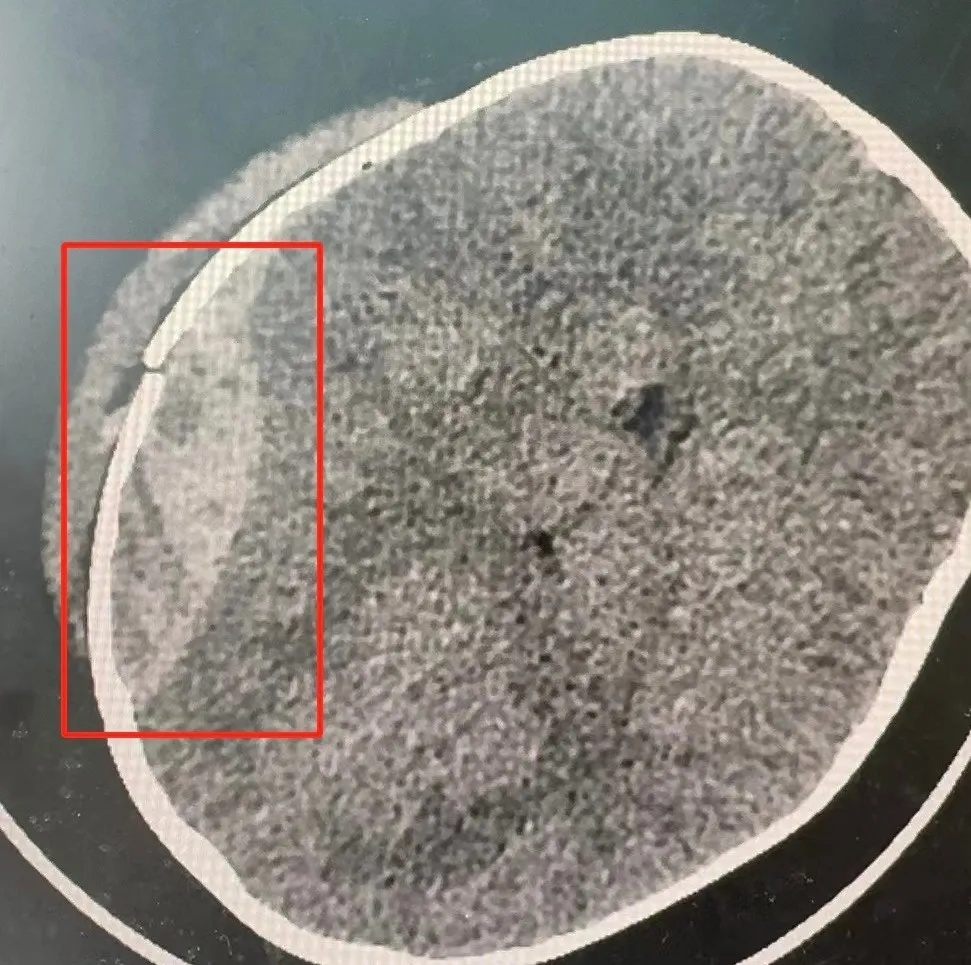

头、胸、腹部CT提示创伤性颅内出血、颅骨骨折,不排除进一步发展的可能性。时间就是生命,医生建议马上转院至青岛妇儿医院进一步诊疗。

入院后,青岛妇儿医院密切观察孩子病情发展,CT检查结果提示创伤性湿肺,创伤性硬膜外出血较前增多,约40ml,符合手术指征,需要马上实施手术!

据悉,创伤性硬膜外出血是一种严重的脑外伤。当出血量增多时,可能会导致颅内压增高、脑水肿等并发症,甚至可能短时间内危及生命。

经过数小时的奋战,手术成功!1天后星星脱离生命危险,拔除气管插管后转回神经外科病房,术后复查头颅CT,颅内血肿清除彻底。目前孩子已经顺利出院……